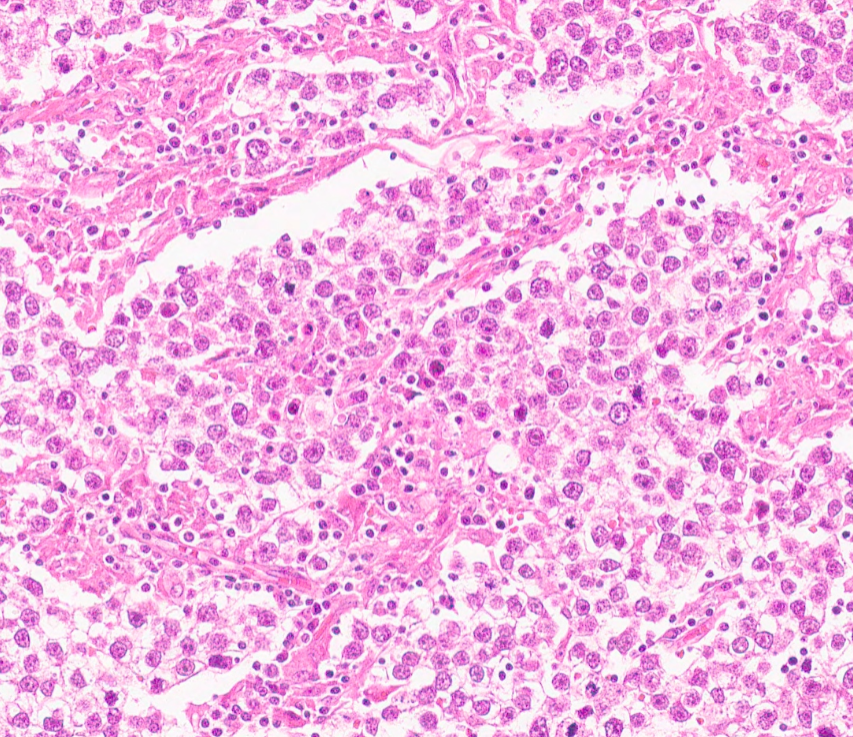

Since 2003, we have been creating one of the largest pathology educational resources online.. completely open access and free to use for non-commercial activities.. please get in touch for educational collaboration or commercial use 👍 any use pls credit: virtualpathology.leeds.ac.uk